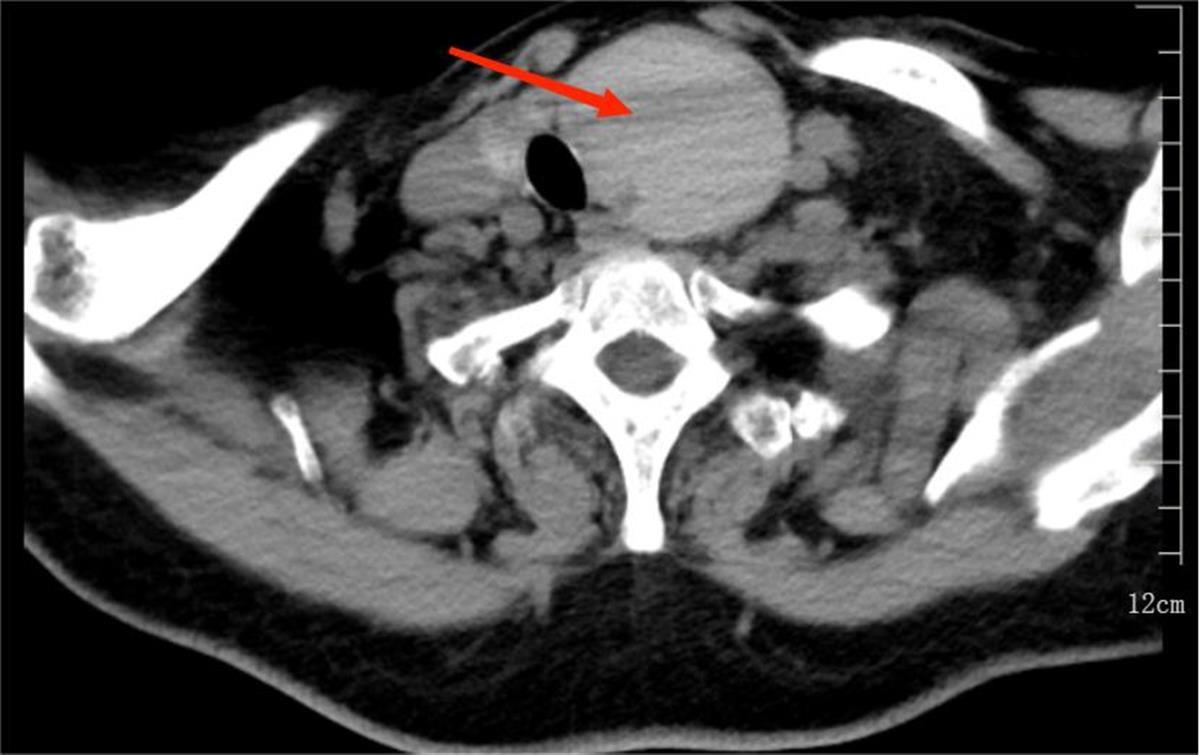

阳婆婆在湖北省中医院进行甲状腺超声造影评估,显示其甲状腺左侧有个约6.2*5.2*3.7厘米的囊性结节,压迫了气管,导致了阳婆婆一系列痛苦的症状。

阳婆婆颈部的囊性结节(通讯员供图)